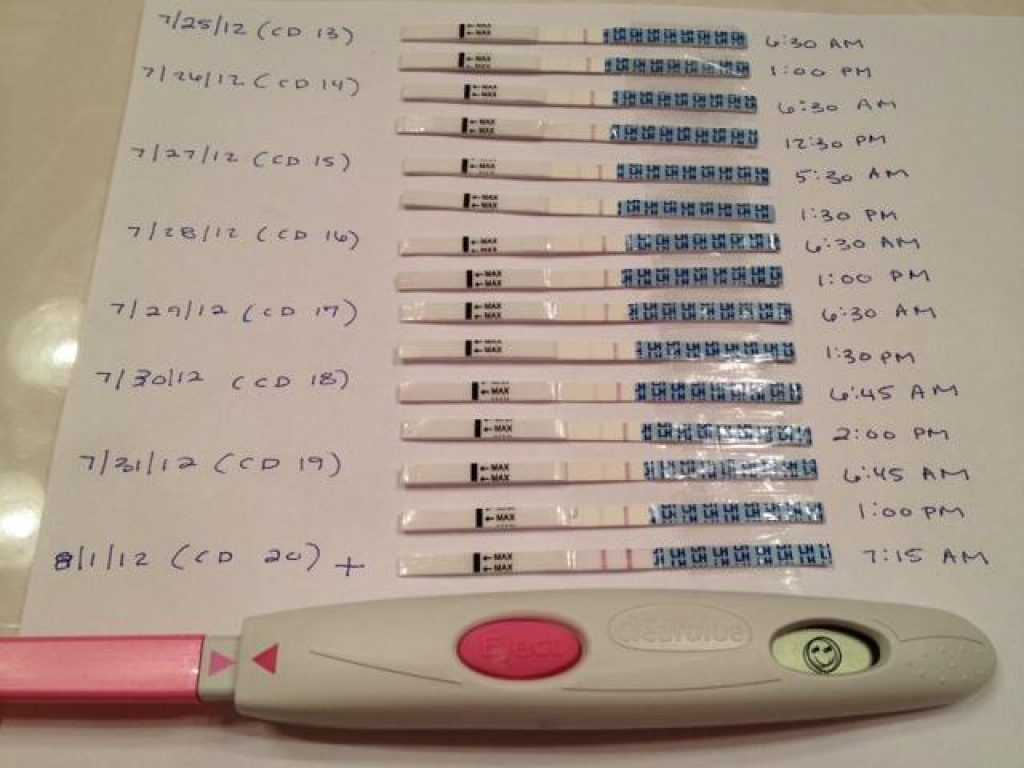

Рекомендации по зачатии